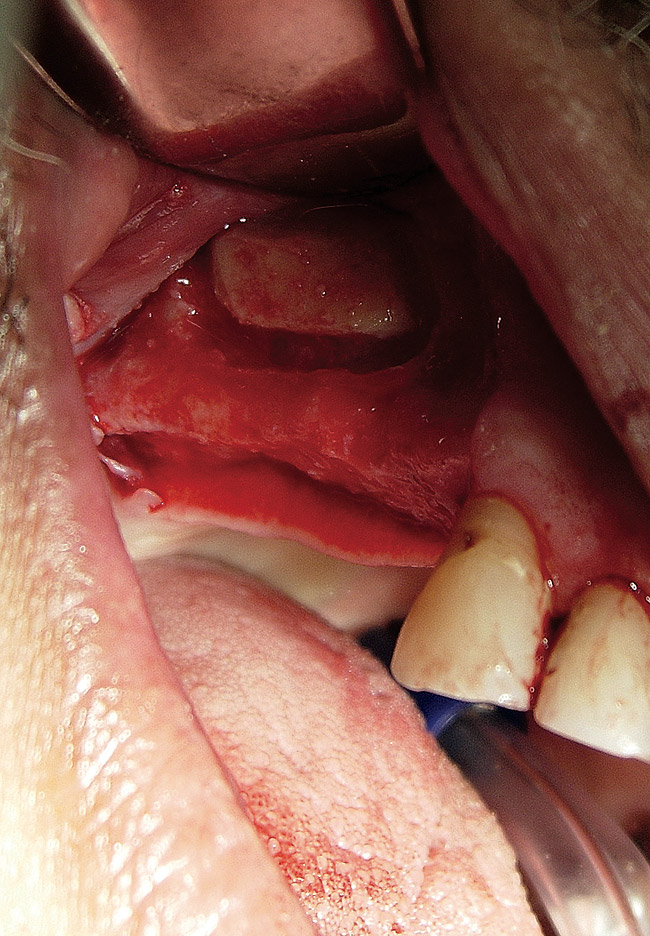

The lateral approach is also used for sinus floor elevation. It is indicated when there is reduced residual bone height, which does not allow standard implant placement or placement of implants in combination with minor sinus floor elevation using the osteotome technique (Figure 1, Figure 2 and Figure 3). Contraindications are excessive interarch distance due to unfavorable crown-to-root ratio, acute or chronic unresolved sinusitis, current sinus pathology (eg, cysts or tumors), lodged root tips in the sinus, history of heavy smoking, a systemic compromise, and psychological problems.

Figure  2  Outline of the lateral window

Figure 2

Figure  3   Elevation of the bony window.

Figure 3